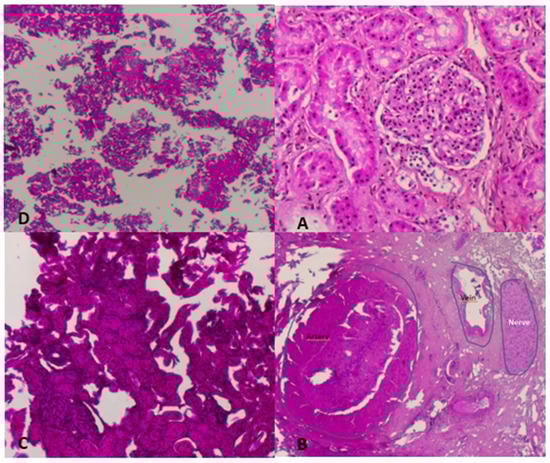

| Group | Time (min) to Complete Ablation. Mean (SD) | Percentage of Non-Affected Tissue | Percentage of Ablated Necrotic Tissue with Recognizable Architecture | Percentage of Destroyed Unrecognized Tissue |

|---|---|---|---|---|

| 1 (1 cm3) | 16.4 (2.7) | 0% | 0% | 100% |

| 2 (1.5 cm3) | 28.1 (2.5) | 0% | 0% | 100% |

| 3 (2 cm3) | 40.3 (3.3) | 0% | 0% | 100% |

| 4 (2.5 cm3) | 53.7 (4.3) | 0% | 8% | 92% |

| 5 (3 cm3) | 69.7 (6.6) | 0% | 15% | 85% |